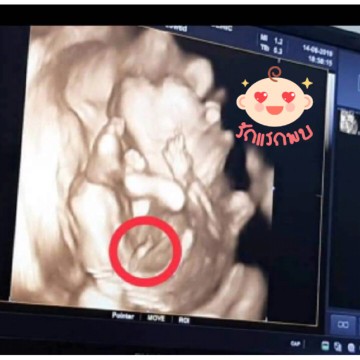

กำหนด22ธันวาคม อยากได้ลูกสาว แต่น้องเป็นผู้ชายจร่าา